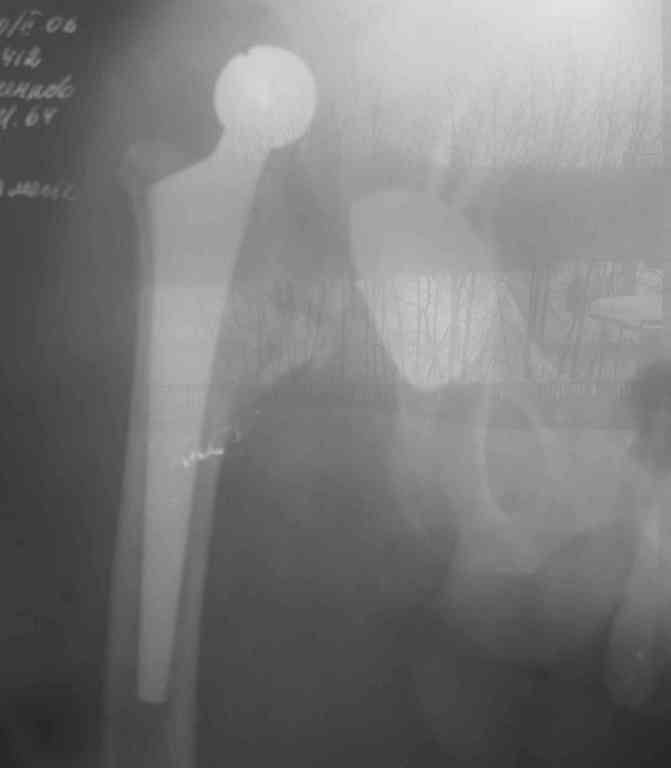

Интересный пример: (см фото)

Вывих эндопротеза на 5 сутки после операции. (причина- ошибки предоперационного планирования и интраоперационные ошибки)

Пациент от ревизии отказался.

Сейчас прошло 4 года после операции. Больной ходит с полной нагрузкой на оперированную конечность с тростью. болей нет.

Извините за плохое качество фото